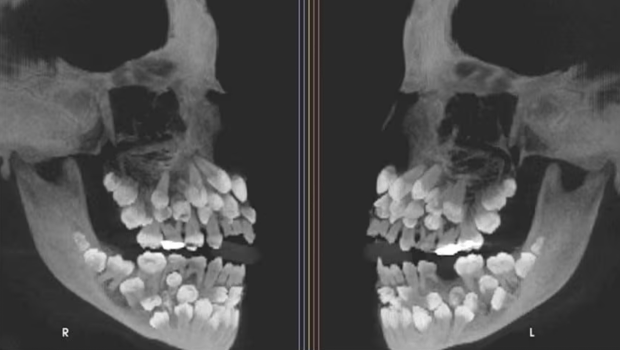

巴西一名11歲女童被發現口內有81顆牙,包括18顆乳牙、32顆恒牙及31顆多生牙(supernumerary teeth),遠超成人正常32顆恒牙的數量。此病例于《美國正畸與牙面骨科雜志》中發表,引起全球學界關注。

▲巴西一名11歲女童被發現口內有81顆牙,包括18顆乳牙、32顆恒牙及31顆多生牙(supernumerary teeth)?!睹绹c牙面骨科雜志》

這名11歲女童因需拔除一顆上頜乳牙而前往朱伊斯迪福拉聯邦大學牙科醫院就診,當時臨床檢查并未發現明顯異常,但X光檢查結果令人瞠目結舌,因揭示其口內共有81顆牙,其后證實女童患有多牙癥。研究團隊進一步使用錐形束計算機斷層掃描(CBCT)確認牙齒的精確位置及形態,發現多生牙分布于牙弓各處,部分深埋于牙齦內,形態異常,難以與正常牙齒區分。